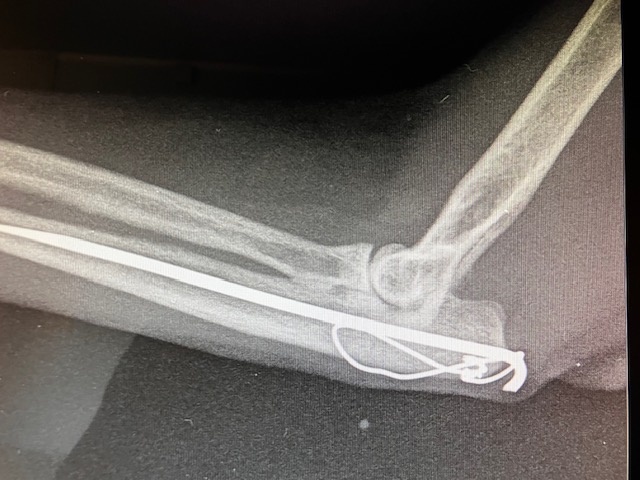

La zone de Fracture s’est écartée, la broche semble pliée, la fracture est instable et ne cicatrise pas correctement. La tension sur cette zone, sur l’olécrane, par la flexion des muscles brachiaux, exercent une forte traction, lors de flexion du coude. Ceci est aggravé par l’activité soutenue de cette jeune chatte. Nous décidons de reposer un pansement – attelle en attendant de ré-intervenir chirurgicalement.

Effectivement, quelques jours plus tard, la propriétaire signale que la chatte boîte fortement sans appui. Nouvelle radiographie : Rupture de l’implant. Sous la tension et la force de traction, la broche métallique, ainsi que le cerclage complémentaire qui devait s’opposer à la force de traction, ont cassé. Il faut reprendre la chirurgie.

Nous utilisons exactement la même technique mais avec du matériel plus résistant. Nous augmentons le calibre de la broche et nous utilisons aussi un fil métallique de cerclage de diamètre plus important. En fin d’intervention, la réduction est satisfaisante.

la broche utilisée étant de diamètre plus important, nous n’avons pas pu la faire pénétrer dans toute la cavité médullaire de l’os ulnaire. Mais cela semble suffisant, nous voulons maintenant une résistance accrue. Pour compléter, l’intervention, nous pososn une contention externe complémentaire, avec une immobilisation du coude et de l’avant bras sous résine.